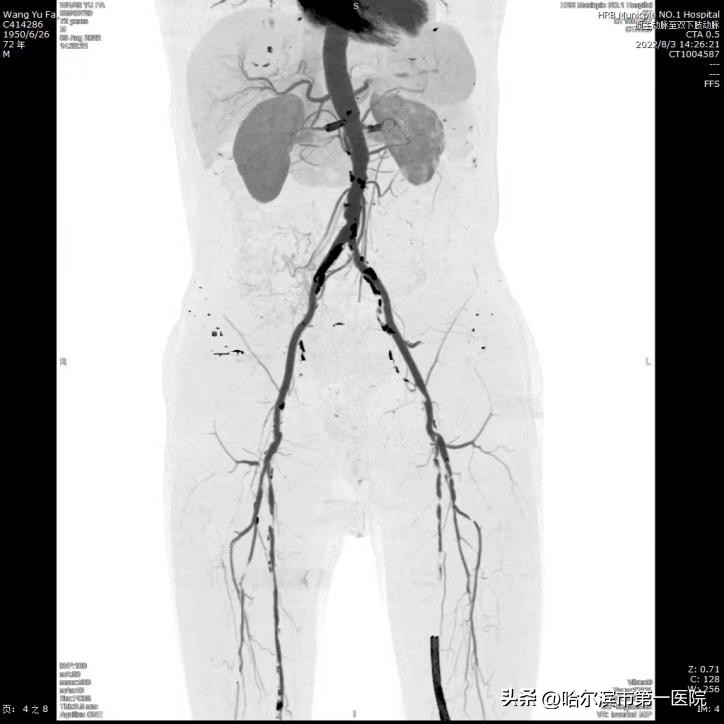

患者王大爷,既往就有高血压、糖尿病史,3年前检查发现左下肢动脉堵塞了,于是做了左下肢动脉支架症状终于缓解。可近一周,老爷子术前的症状再次出现,而且比之前的症状更加严重了。剧烈的疼痛折磨得王大爷整日坐卧不宁,彻夜不眠。儿女们很困惑,刚做完手术没几年怎么又出问题了呢?经多方打听,王大爷来到了哈尔滨市第一医院血管外科寻求医治。

医生为王大爷进行了详细的问诊和查体。结合患者以往的症状和做过动脉支架的手术史,首选考虑患者是左下肢动脉支架内血栓形成。通过下肢动脉CTA结果证实了判断。以往处理支架内血栓需要开刀手术,切开取栓或者选择支架内再次支架,往往导致术后并发症,严重的病人可能出现肢体坏死截肢,甚至危及生命。经过与家属的充分沟通,决定采取目前先进的动脉机械吸栓(Rotarex)技术帮助老人解决目前的难题。不仅可以让王大爷避免麻醉的风险,也让术后的皮肤无创降低感染几率。